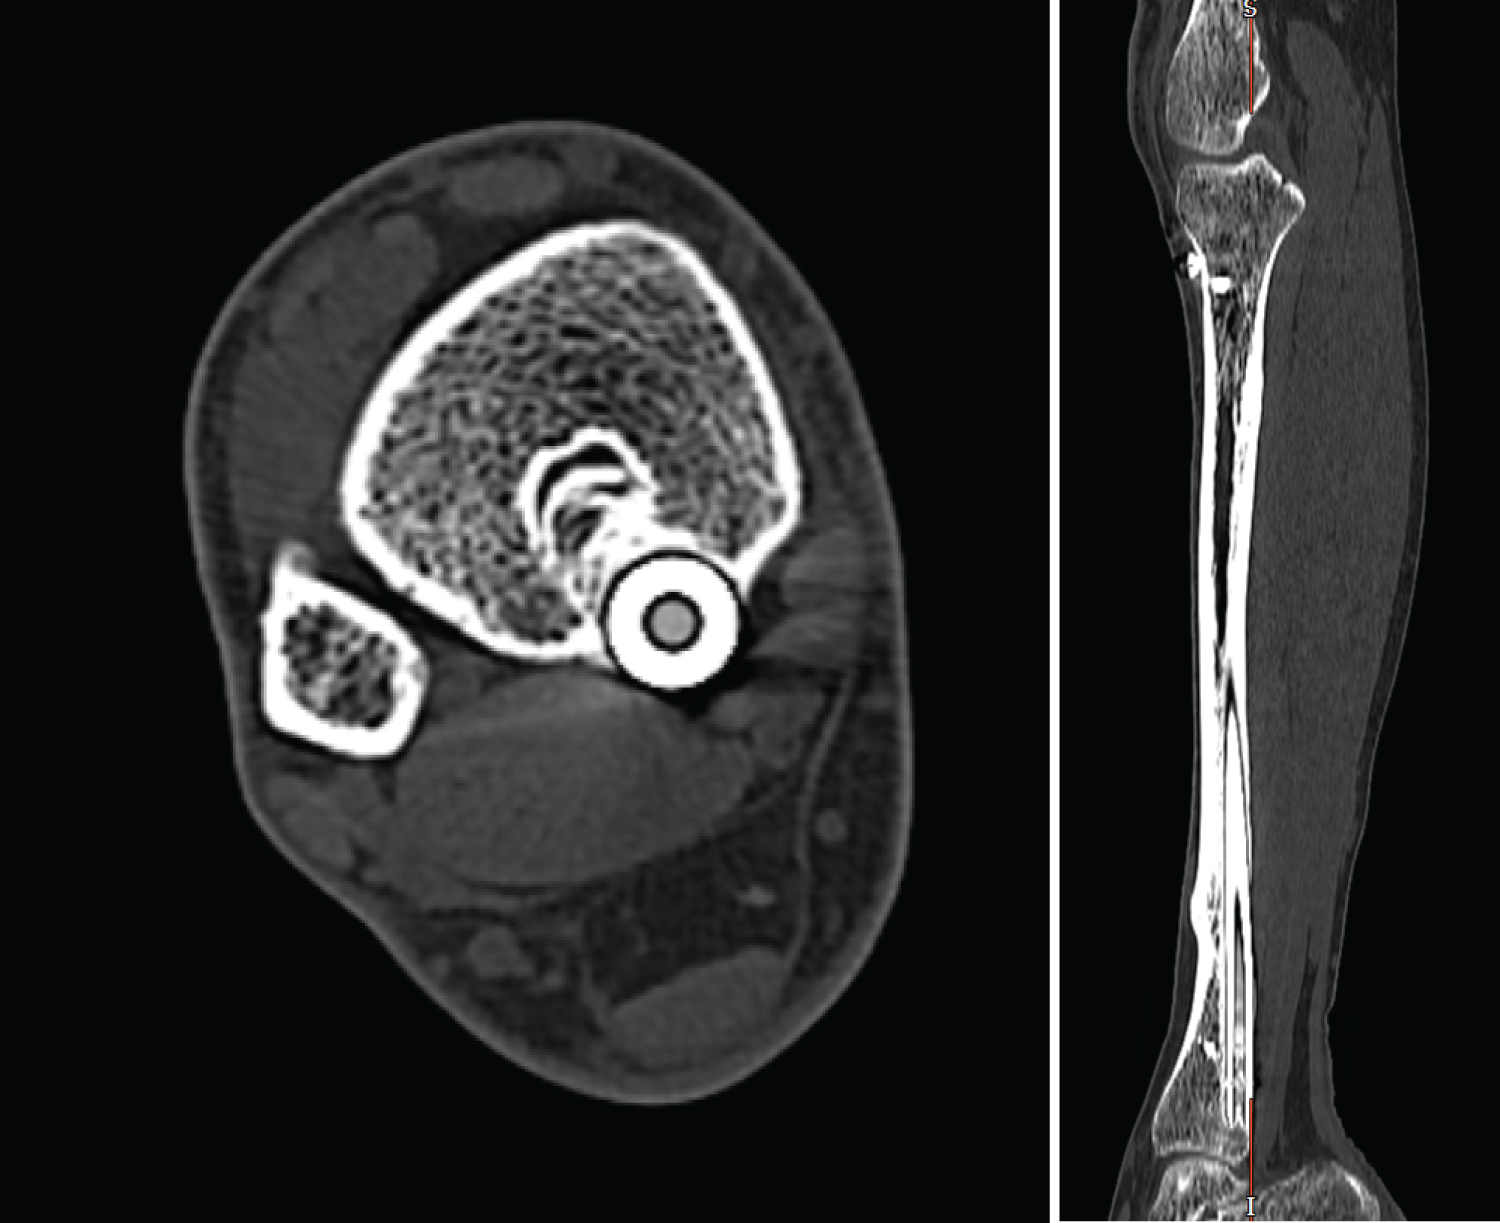

On review, the patient's wounds had healed and there was no evidence of infection or swelling and the fracture site remained non tender with no evidence of motion or erythema. Mildly reduced dorsiflexion and an antalgic gait remained the only positive findings on examination. Radiographs taken following clinical review demonstrated distal nail protrusion into the deep posterior compartment posteriorly, with appropriately sited proximal nail with two bi-cortical bolts in-situ (Figure 4). Blood tests to investigate for infection, Bone profile and an ESR returned within normal limits, other than an elevated ALP suggesting higher than normal bone turnover. A CT scan confirmed migration through the posterior cortex distally abutting the belly of flexor hallucis longus (Figure 5).

Figure 4: AP + Lateral X-ray showing distal protrusion of IM nail 10 years post distal locking screw removal. View Figure 4

Figure 5: CT Axial and Sagittal view showing distal protrusion of IM nail 10 years post distal locking screw removal. View Figure 5